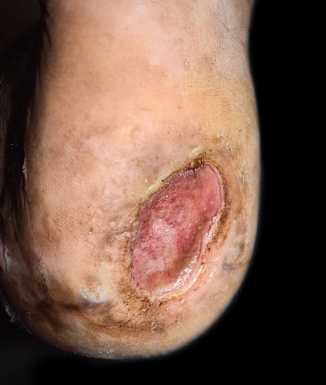

Wound healing is a dynamic and complex physiological process, and successful progression depends on adequate wound bed preparation. Debridement plays a central role in this phase, eliminating devitalized tissue that impedes healing and harbors infection. Sharp debridement—using sterile instruments such as a scalpel, scissors, or curettes—is rapid and precise, making it the preferred method for most chronic wounds. However, it is not universally applicable, and clinicians must recognize situations where alternatives may be safer and more effective.

Sharp debridement is contraindicated in a variety of clinical scenarios. Patients with peripheral arterial disease (PAD) may experience exacerbated ischemia or worsening of tissue necrosis due to inadequate blood flow. Pain, particularly in patients with venous leg ulcers (VLUs), can render sharp debridement intolerable. Mobility limitations or logistical barriers such as lack of access to wound care clinics, surgically trained health care providers, or appropriate instrumentation also pose challenges. Moreover, patients with comorbid conditions—including anemia, autoimmune diseases, or diabetes mellitus, among others, and those on anticoagulant therapy—could face elevated risks of bleeding and further impaired wound healing.1

Autolytic debridement. This method uses moisture-retentive dressings to activate the body’s own enzymes. Though slow, it is painless and selective, making it suitable for noninfected, low-exudate wounds. A systematic review of 5 randomized controlled trials involving 236 patients by Amadeh and colleagues aimed to evaluate and compare the clinical effectiveness of autolytic debridement and collagenase-based enzymatic debridement in managing chronic wounds such as diabetic foot ulcers (DFUs), pressure ulcers, venous leg ulcers, and burn injuries.3 This recent review found that the autolytic method remains a valuable option for less severe wounds due to its noninvasive and pain-free nature including palliative and home care settings, with lower tissue trauma compared to mechanical options.3